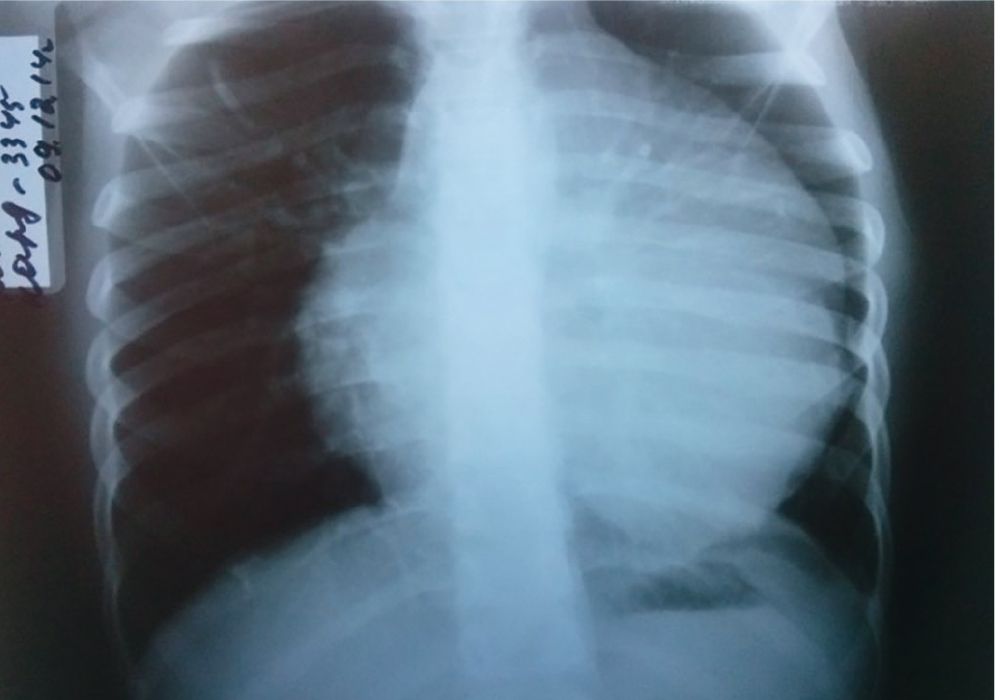

Рентгеновские снимки тератомы средостения: Диагностика и лечение

Раздел: Фотоэссе